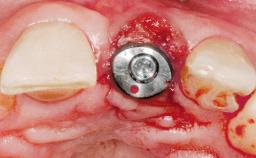

Immediate Placement of an Implant in a Maxillary Right Central Incisor Site

A 30-year-old female patient was referred to the office for the treatment of tooth 11. Her chief concern at the initial visit was to inquire, “Why is my tooth pink?” Upon clinical examination, it was determined that tooth 11 had a previous history of trauma and that the clinical crown had become noticeably pink in color as a result of internal resorption. This diagnosis was confirmed radiographically, indicating a large radiolucency involving the central and distal portions of the clinical crown. It was determined that restoration of this tooth was not possible, and that extraction was indicated. The presence of a mid-line diastema, which the patient wanted to reproduce, directed the treatment plan for tooth replacement utilizing a dental implant.

# of Implants 1

Type of Implants One-Piece|Reduced-Diameter

Placement Protocol Immediate implant placement

Tooth Site Maxillary incisor or canine

Socket Morphology Single-root socket

Socket Integrity Sufficient, with intact bone walls

Bone Volume Sufficient, with intact walls